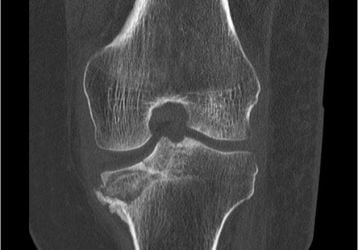

Асептический некроз коленного сустава: классификация, диагностика, лечение

Асептический некроз коленного сустава, что это такое, как диагностируется и способы лечения. Медикаменты, физиотерапия и хирургические операции.